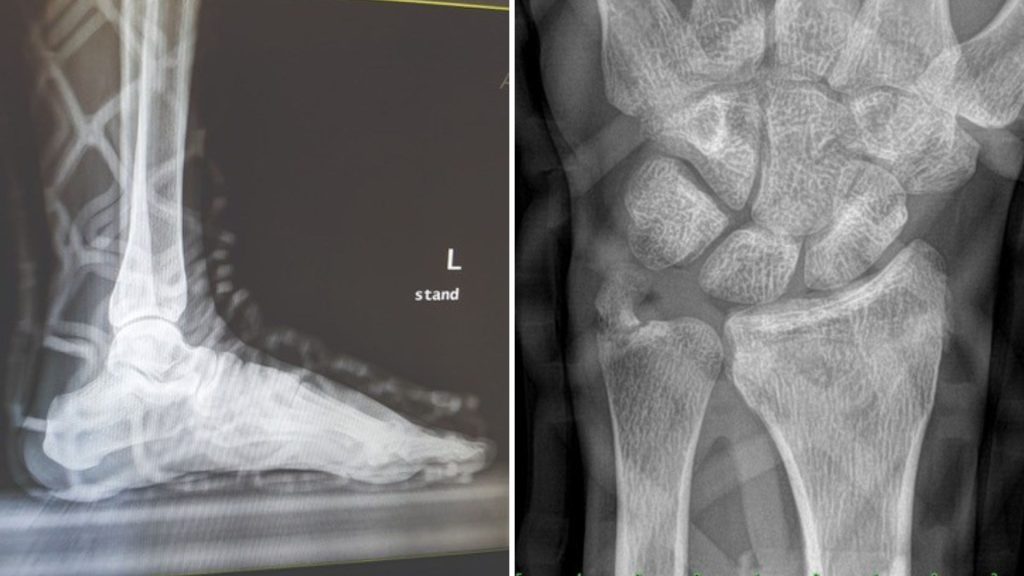

3. Problemy z diagnostyką i prześwietleniami (RTG)

Monitorowanie zrostu kości to podstawa leczenia ortopedycznego. Niestety, klasyczne opatrunki oraz niektóre grubsze usztywnienia z włókna szklanego znacząco zaburzają obraz rentgenowski. Aby uzyskać wyraźne zdjęcie i upewnić się, że nie doszło do wtórnego przemieszczenia odłamów, bardzo często trzeba zdejmować cały opatrunek. To procedura stresująca, czasochłonna i generująca dodatkowe koszty związane z koniecznością ponownego założenia stabilizacji.

Rozwiązanie Opencast Lite: Materiał użyty w Opencast Lite jest w pełni radioprzezierny – przepuszcza promienie rentgenowskie. Dzięki temu kontrolne prześwietlenie RTG przez opatrunek jest wysoce czytelne, a lekarz diagnozuje postępy leczenia bez konieczności niepotrzebnego zdejmowania stabilizatora.